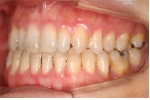

日本矯正歯科学会専門医課題症例(第7症例)

カテゴリー:開咬(overbiteがマイナスのもの)

| 初診時